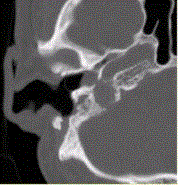

问题 患者男,54岁,右侧耳部不适,耳镜检查示蓝色鼓膜。HRCT显示如下图。 可能的诊断为

选项 A.颈静脉球瘤 B.颈静脉孔区神经鞘瘤 C.颈静脉孔区脑膜瘤 D.中耳乳突炎 E.中耳胆脂瘤

答案 A